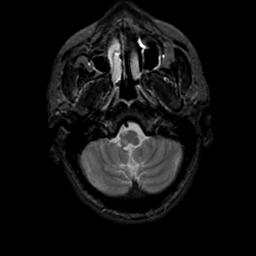

MR Study #22, December 1, 1991 -- Slice #7